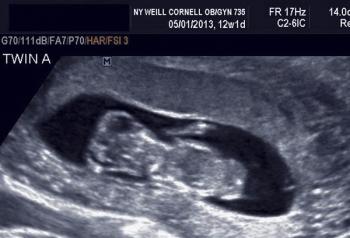

Early imaging is key to the diagnosis of the many anomalies that are unique to multifetal gestations. The third slideshow of our ultrasound collection includes examples of these anomalies.